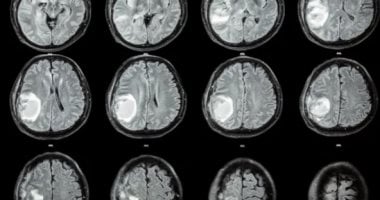

في حالة نادرة للغاية ، قام الأطباء بإزالة الجنين الجراحي من دماغ فتاة أمريكية واحدة ، ووجد الأطباء الجنين بعد أن أظهر الطفل تأخيرًا في تطوير المهارات الحركية ، ومحيط رأس مُضطر وتراكم السوائل في الدماغ ، وفقًا للعلم الحي ، وخلال سلسلة “الأجنحة في الحكايات”.

أشار تقرير نُشر في مجلة الأعصاب إلى أن الكتلة الموجودة في رأس الفتاة الصغيرة كانت “من المشيمة الواحدة المليئة بالتوأم” ، مما يعني أنه في الرحم ، كانت الأجنة قد شاركت نفس المشيمة ولكنها كانت لها أوجه تشابه منفصلة ، وهي أكياس جدار رقيقة وسوائل تحيط بالأجنة أثناء نموها.

هذه الحالة الشاذة التي يلف فيها الجنين آخر جنينًا آخر باعتباره “الجنين داخل الجنين” ، أو في بعض الأحيان “توأم طفيلي” ، فإن التوأم الذي يتوقف عادة ينمو بينما يستمر الآخر في النمو ، وفقًا لصحيفة ميامي هيرالد.

تحدث هذه الظاهرة في 1 من كل 500000 ولادة حية ؛ عادة ما يظهر الجنين المشوه ككتلة في بطن الجنين الآخر ، محشورًا خلف الأنسجة التي تصطف على جدار البطن.

ومع ذلك ، في هذه الحالة ، ظهرت الكتلة في رأس الجنين “المضيف” ، ومن المحتمل أن تكون نشأت في وقت مبكر جدًا في النمو ، في المرحلة التي تكون فيها البيضة المخصبة هي مجموعة من الخلايا تسمى كيس الأسلحة.

قال الباحثون إن “داخل الجمجمة يتم إنشاؤها من الخراجات الأريمي دون انقطاع” ، مما يعني أن مجموعات الخلايا التي كانت تنمو إلى جنينين منفصلين ظلت مرتبطة ببعضها البعض.

تتطور الأجزاء المتصلة إلى الدماغ الأمامي للجنين المضيف وتغطي الجنين الآخر أثناء طي لوحة الأعصاب (لوحة الأعصاب هي بنية تتشكل في التطور المبكر وتؤدي إلى ظهور الجهاز العصبي.

أشار تقرير الحالة لعام 2020 في مجلة جراحة الجراحة العصبية العالمية أيضًا إلى أن الجزء الداخلي من الجنين داخل الجمجمة نادر للغاية مع نشر أقل من 20 تقريرًا في هذه الحالة في جميع أنحاء العالم.